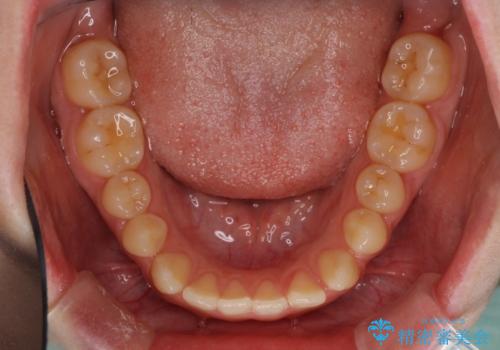

上顎骨を拡大したことで、下顎の歯列を上顎が受け入れられるようになりましたが、インビザラインでは咬み合わせを改善させることができなかったため、ワイヤー矯正にて仕上げることとしました。

ワイヤーを使用したものの、上下前歯のオープンバイトがなかなか改善されませんでしたが、患者希望により治療終了となりました。